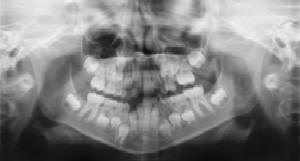

Radiographs (X-Rays) are a vital and necessary part of your child's dental diagnostic process. Without them, certain dental conditions can and will be missed.

Radiographs detect much more than cavities. For example, radiographs may be needed to survey erupting teeth, diagnose bone diseases, evaluate the results of an injury, or plan orthodontic treatment. Radiographs allow dentists to diagnose and treat health conditions that cannot be detected during a clinical examination. If dental problems are found and treated early, dental care is more comfortable for your child and more affordable for you.

The American Academy of Pediatric Dentistry recommends radiographs and examinations every six months for children with a high risk of tooth decay. On average, most pediatric dentists request radiographs approximately once a year. Approximately every 3 years, it is a good idea to obtain a complete set of radiographs, either a panoramic and bitewings or periapicals and bitewings.

Pediatric dentists are particularly careful to minimize the exposure of their patients to radiation. With contemporary safeguards, the amount of radiation received in a dental X-ray examination is extremely small. The risk is negligible. In fact, the dental radiographs represent a far smaller risk than an undetected and untreated dental problem. Lead body aprons and shields will protect your child. Today's equipment filters out unnecessary x-rays and restricts the x-ray beam to the area of interest. High-speed film and proper shielding assure that your child receives a minimal amount of radiation exposure.